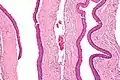

التشخيص النهائي عن طريق التحليل النسيجي ، أي الاستئصال وفحصها تحت المجهر . تشبه الأغشية الحرشفية الكيراتينية بغموض .[2]

ومع ذلك فإنها تفتقر إلى الحواف , و غالبا ما يكون هناك تحت المجهر , غالباً فصل انفصال عن الغشاء القاعدي المحيط بهم .

Intermed. mag.